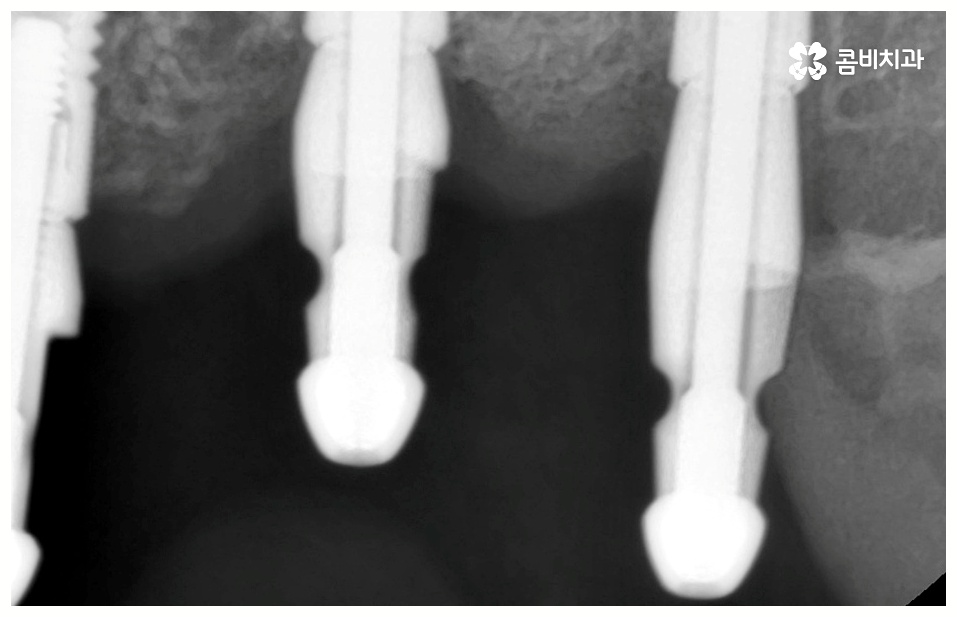

뼈이식은 각자에게 맞는 골이식재료 가루를 생리식염수에 반죽하여 빈 공간에 채워넣으면 이를 이용하여 우리의 세포가 잇몸뼈를 만들어내는 골융합 과정을 의미하는데 회복 시간을 충분히 주어 무리가 가지 않도록 진행을 해야 안정성과 지속성을 높일 수 있기 때문에 임플란트 치료기간 자체를 줄이는 데 초점을 맞추는 것보다는 필요한 처치들을 꼼꼼하게 해 주는 것에 초점을 맞추시는 게 필요할 거예요.

임플란트 치료는 자신의 자연 치아를 대신해 오랫동안 쓸 수 있도록 장기적인 안정성을 추구하는 것이 중요하기 때문에 최초의 진단과 치료 계획을 꼼꼼하게 세우는 것이 필수라고 할 수 있어요.

또한 풍부한 임상 경험과 노하우를 가진 숙련된 의료진, 다각적이고 체계적인 분석을 할 수 있는 3D CT 와 같은 정밀 분석 장비를 갖추고 보다 안정성이 검증된 정품 재료의 사용 여부 등을 잘 체크해야 할 거예요.